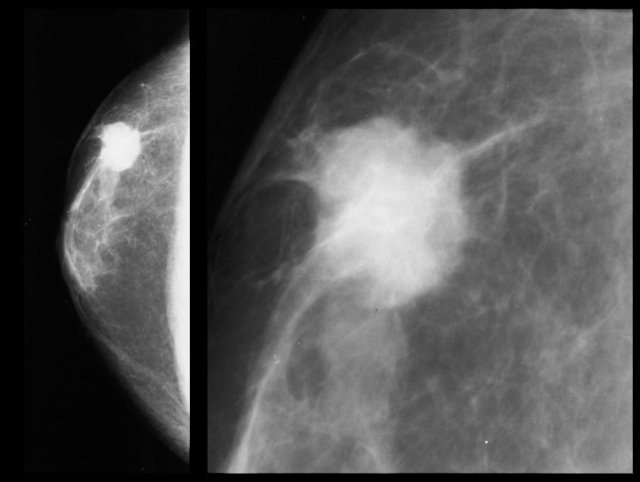

Invasive ductal carcinoma Invasive ductal carcinoma

On the left an eccentric irregular mass with spiculae.

If this was a women you would have no trouble in diagnosing this as a cancer. In a man it is the same.